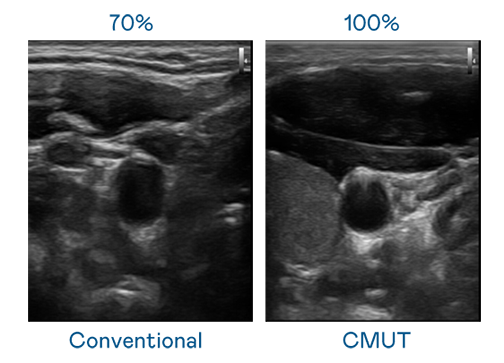

CMUT 技术是一种用电容式微机电元件来产生超音波讯号的技术。与传统 PZT 压电式技术相比,CMUT 频宽增加 30%,更宽频的超音波讯号让影像解析度大幅提升,是实现高影像品质医疗超音波扫描、促进精准医疗发展的关键技术。

大频宽带来超清晰影像

超音波影像的解析度高低,首先取决于探头能发出的讯号频宽。u8国际 CMUT 可提供高清晰的超音波讯号,提供高频宽、高灵敏度、影像纹理细节更高的超音波影像,协助医护人员缩短影像判读时间及利用精准的医疗影像进行诊断。